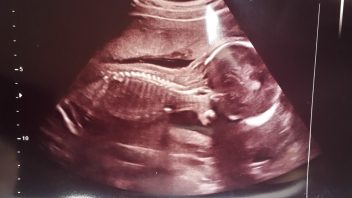

TĚHULKA HELENA Minulý týden jsme se na ultrazvuku dozvěděli tu velkou novinku, že čekáme kluka. Nemůžu se z toho šoku stále vzpamatovat. Byla jsem od začátku psychicky nastavená na holčičku. Už jsem se viděla, jak ji budu oblékat do růžových šatiček a střevíčků a jak si spolu budeme hrát holčičí hry, které jsem já jako malá milovala. Jen o jménu pro holčičku jsem neměla ani tu nejmenší představu, pro holčičku se mi nelíbilo nic.